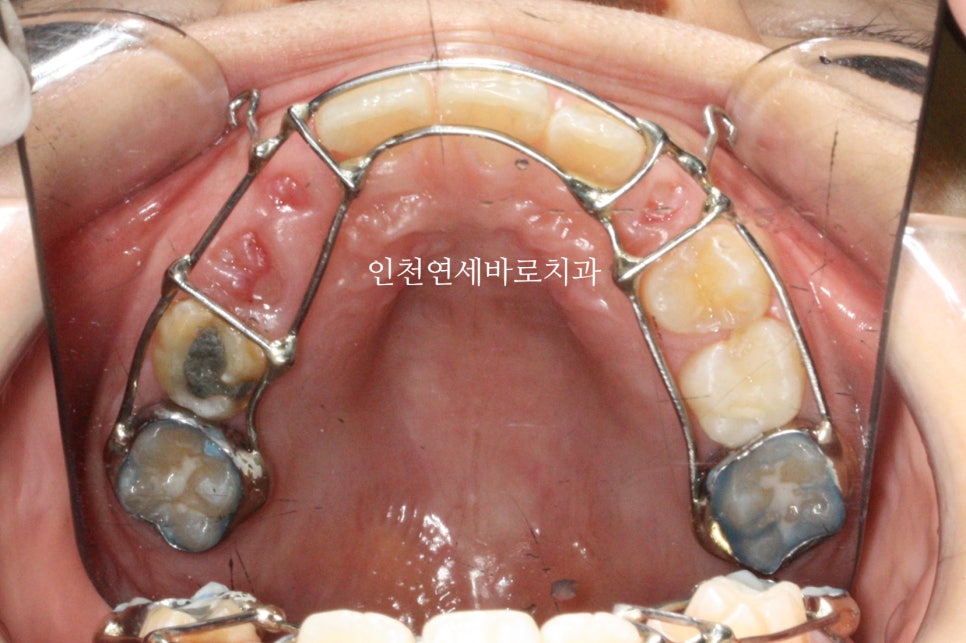

처음에는 페이스마스크를 사용했습니다.

주걱턱 교정에 사용하는 장치지만, 그 목적으로 사용한 것은 아닙니다.

잠시 페이스마스크를 사용했고, 이후 치아의 위치들을 바꿔주기 위한 구내장치도 사용했습니다.

장치의 세부 목적은 생략할께요

이렇게 준비를 하고 나서 2차교정이 시작되었습니다.